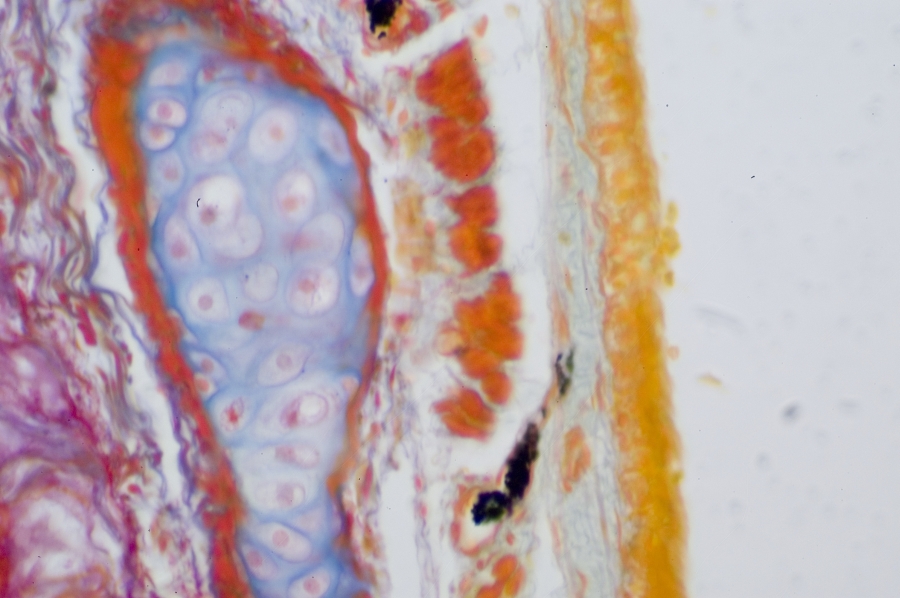

Image Filename: 36931_4524-3

36931_4524-3

container invno 36931

specimen id 4524